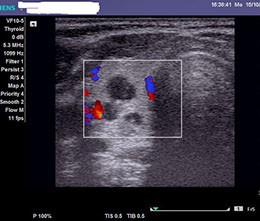

- Ультразвуковое исследование (УЗИ) — это первый и наиболее распространенный метод диагностики. УЗИ позволяет получить изображение почек и оценить их форму, размер и расположение. Этот метод безопасен и не требует использования радиации, что особенно важно для детей.